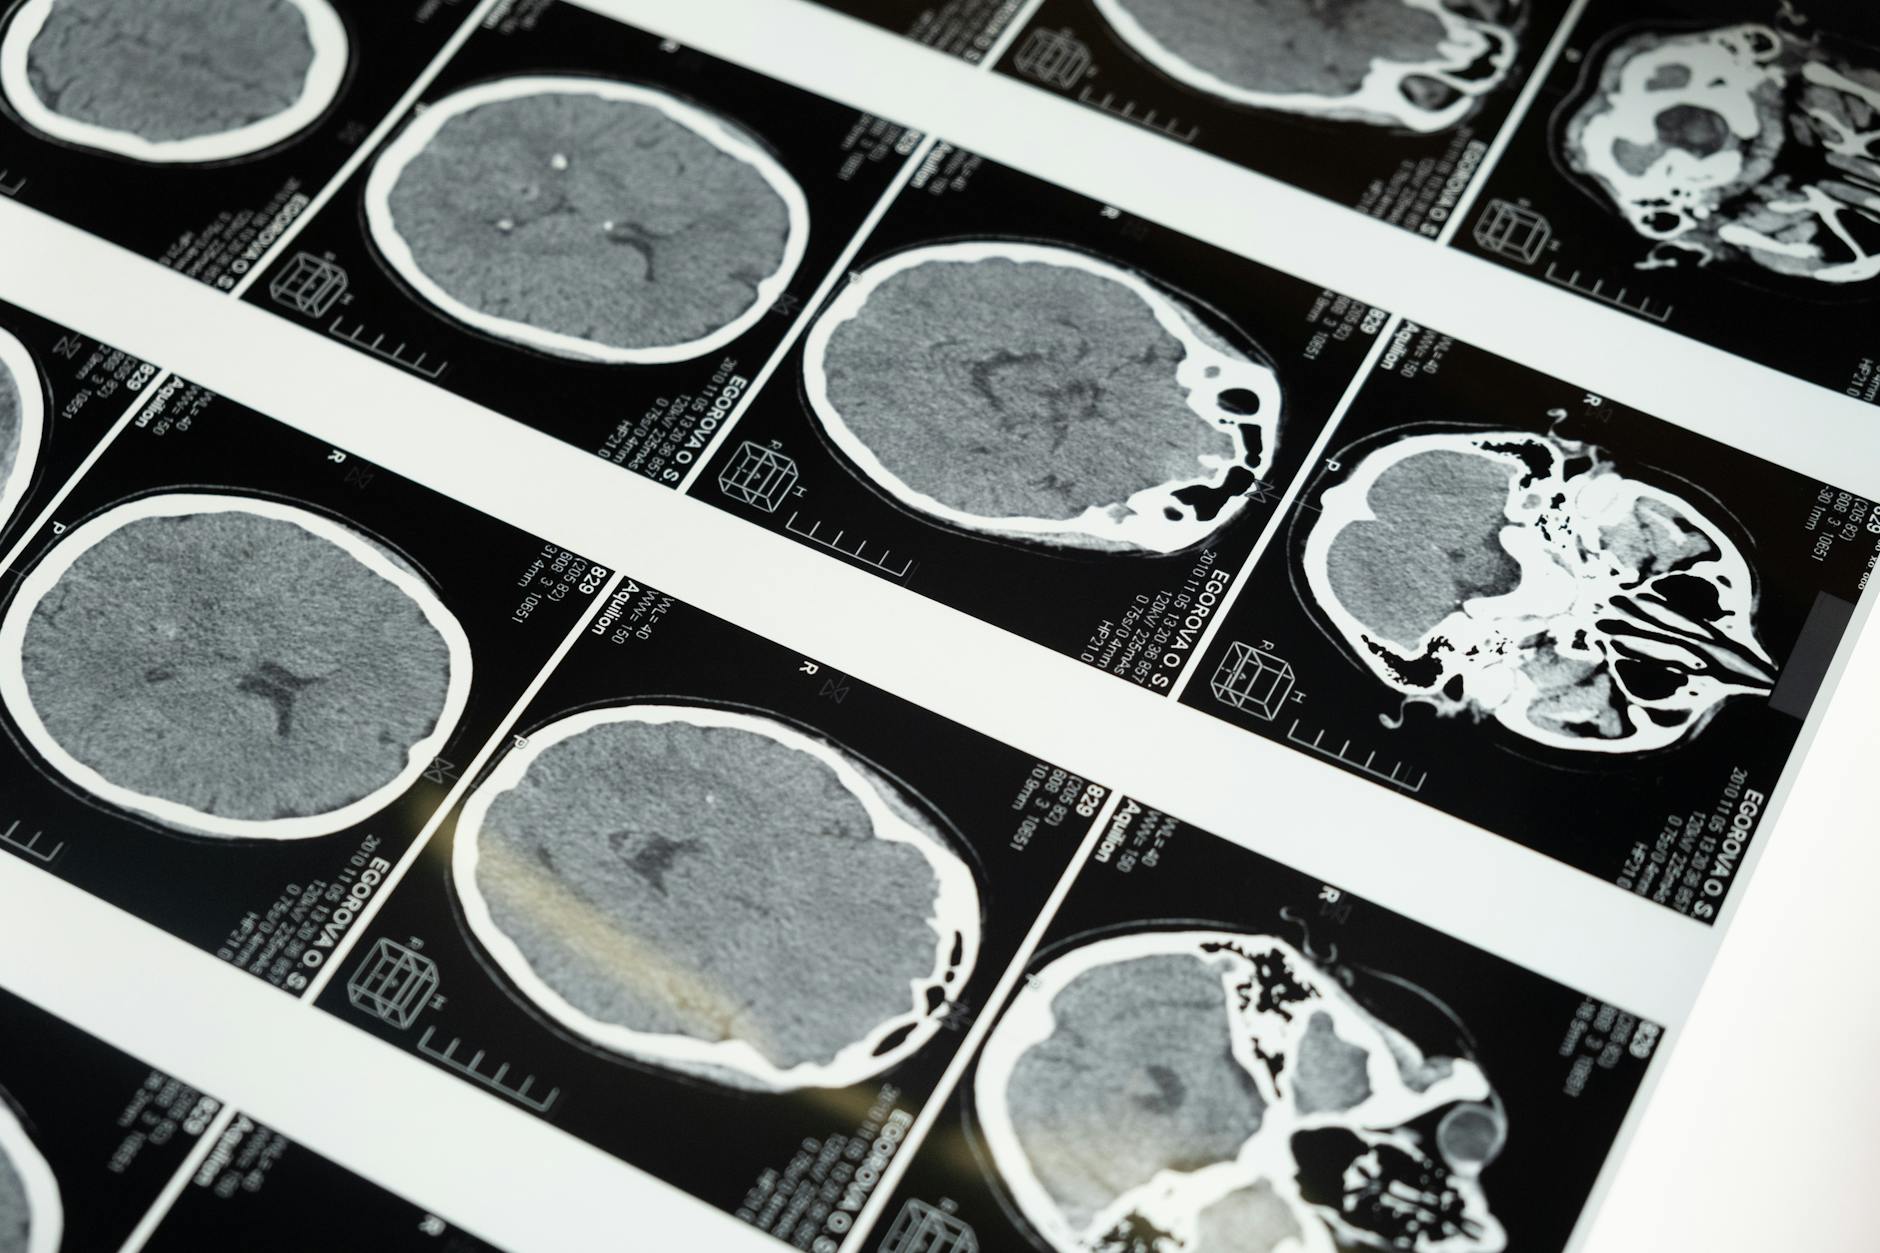

Alison Reidy, de 38 años, despertó con un dolor terrible y no sabía que estaba sufriendo un derrame cerebral. Ahora busca mejorar la conciencia sobre los derrames cerebrales en el Territorio del Norte.

La falta de conciencia sobre los síntomas del derrame cerebral es un problema grave en el Territorio del Norte. La historia de Alison Reidy es un ejemplo de la importancia de reconocer los síntomas y buscar ayuda médica de inmediato.

La conciencia sobre los derrames cerebrales es crucial para prevenir daños irreparables. La historia de Alison Reidy es un recordatorio de la importancia de la conciencia y la acción rápida en caso de un derrame cerebral.